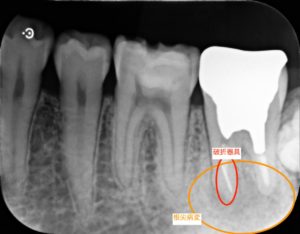

治療後

左下第二大臼歯部に不良補綴物をみとめたため、レントゲン検査を行うと根尖部透過像がみられた。根管内に破折器具がみられたため、破折器具の除去および根管内の感染除去を行った。経過観察後、根尖部透過像の縮小をみとめたため、歯冠修復を行った。

根管治療終了直後

根管治療の偶発症として、使用する器具の破折があります。破折器具は根管治療の妨げになる場合があり、治療中に除去を試みることがあります。根管治療の目的は感染源を取り除くことであり、破折器具そのものが感染源になるわけではありません。そのため破折器具を取り除かなければ病変が治癒しないわけではありません。重要なのは感染源を取り除くことにあります。また、破折器具を取り除くために健康な歯を大きく削らなければいけない場合もあり、破折器具を取り除くことが歯の延命に必ずしも直結するわけではありません。

今回の症例では根管内の汚染が強く、破折器具もはじめからしっかり見えたことから超音波切削器具と次亜塩素酸ナトリウム等を用いて除去しました。再度根管充填を行ったあと、病変の縮小をみとめた後に歯冠修復を行いました。